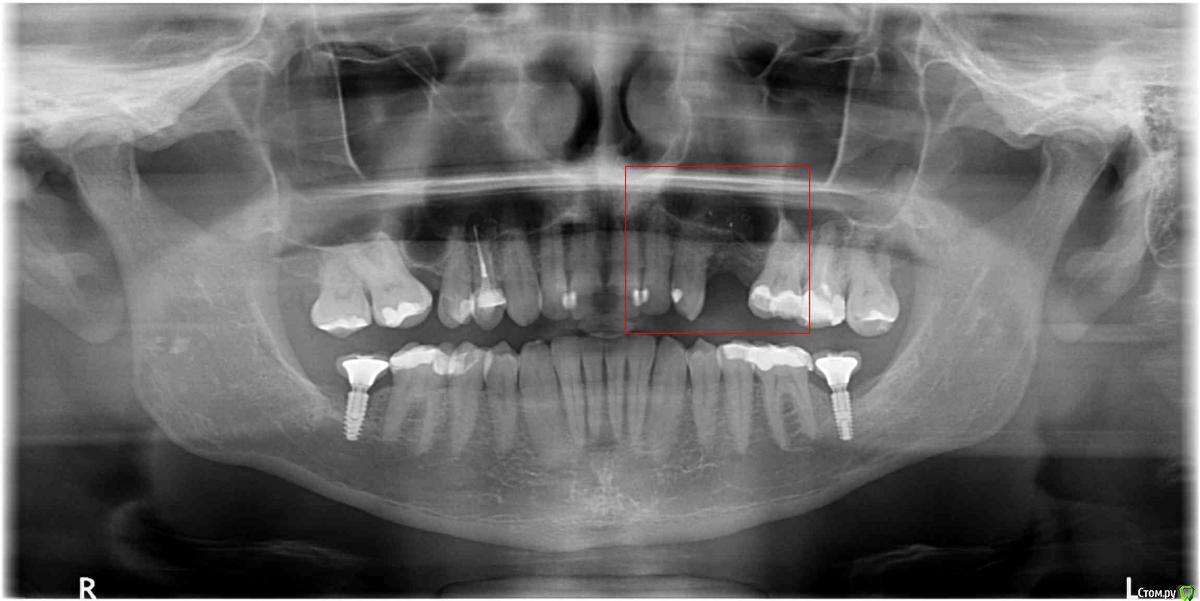

tonkin Опубликовано 9 января, 2017 Поделиться Опубликовано 9 января, 2017 Помогите определиться с числом имплантов. Отсутствуют 2 верхних зуба (в красном квадрате на пано). Расстояние между корнями ~ 16.5 мм. Вопрос следующий, какой вариант лучше (оба после планируемого синус лифтинга): 1) поставить 1 толстый имплант по центру с двойной коронкой, чтобы изобразить 2 зуба под улыбку. Тут смущает то, что в прошлом году уже такой вариант делали. Имплант расшатался за 3 месяца, и выпал (снимок импланта был сделан за 2 месяца до паноромного, где импланта уже нет). Вероятно, что имплант был коротковат для такой нагрузки (да и кости мало), и если сделать лучше, то будет держать двойную коронку нормально. 2) второй вариант - 2 тонких импланта с индивидуальными коронками, но места маловато (4 мм + 3 мм + 4 мм + 3 мм + 4 мм = 18 мм < 16.5 ). То есть все очень впритык. Смущает значительная добавочная стоимость, но с другой стороны, шатающегося импланта как в первом случае уж очень хочеться избежать. Мнения? И если стоимость - не вопрос, то будут ли 2 импланта лучше 1-го ? Дополнительный вопрос - как выглядят 2 нижних импланта на предмет качеста кости. Имплантам - 13 месяцев, коронкам - 7. Эти вроде пока держатся (тфу-тфу). Заранее благодарю за консультацию! Ссылка на комментарий

tonkin Опубликовано 6 июня, 2018 Автор Поделиться Опубликовано 6 июня, 2018 Вот еще 2 пано, с наращенной костью до имплантов, и после, когда уже все зажило. Ссылка на комментарий

dok1 Опубликовано 6 июня, 2018 Поделиться Опубликовано 6 июня, 2018 Надо бы срез кт ближнего импланта с клыком. Близковато кажется. А так ничего вроде. Всё по уровню. Ссылка на комментарий